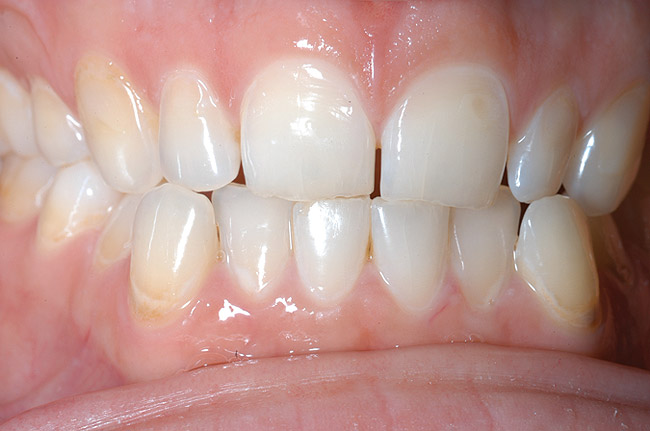

Figure 1  Early enamel loss and some dentin exposure along the cervical margins of the teeth. The cause in this case was identified when the patient admitted to toothbrushing immediately after drinking pure orange juice.

Figure 1

The first signs of tooth wear may not be immediately recognizable because changes to the enamel surface can be difficult to diagnose. The mamelons on the incisal edge of incisors wear away within the first decade after eruption, but other less obvious changes also occur (Figure 1). The cusp tips of molars and premolars may flatten as may the facial surfaces of upper incisors. If allowed to progress, eventually the enamel is worn away, exposing small areas of dentin (Figure 2). Dentin exposure is much easier for dentists to recognize, but it means that considerable amounts of the tooth have been lost. Ideally, therefore, early diagnosis should help to prevent the lesion from progressing into dentin. If the process of tooth wear continues without intervention, almost total destruction of the tooth can occur (Figure 3).